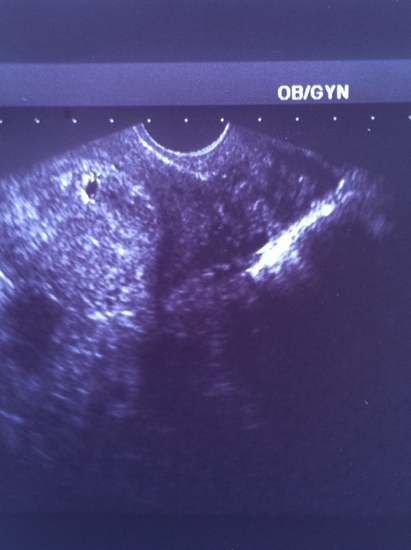

"Да, Вы сейчас тоже увидите," - ответила она и повернула ко мне монитор. Там действительно четко визуализировалась черная горошинка. "Три-четыре недели, я бы сказала. Нормальные контуры. Обычное место расположения. Вот, пожалуй, и все, что я пока могу Вам сказать".

А вот, собственно, и наша горошина. В нее мы верим. Мы ее уже любим. И хотим, чтобы она жила. И была здорова!